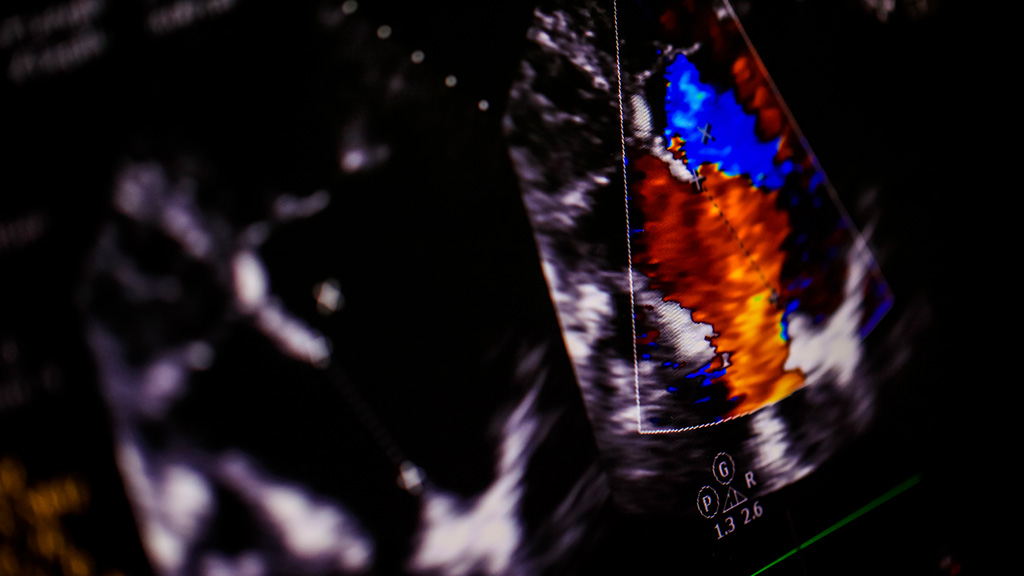

Ultrasonido Codo